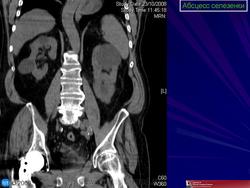

Селезёнки патология. Пнд, 09/09/2013 - 22:59 #1 Катенёв Валенти... Не на сайте Был на сайте: 7 лет 4 месяцев назад Зарегистрирован: 22.03.2008 - 22:15 Публикации: 54876 Спленомегалия Figure 46: Splenomegaly, contrast enhanced CT Пнд, 09/09/2013 - 23:00 #2 Катенёв Валенти... Не на сайте Был на сайте: 7 лет 4 месяцев назад Зарегистрирован: 22.03.2008 - 22:15 Публикации: 54876 Киста селезенки Figure 48: Spleen cyst, contrast enhanced CT Пнд, 23/09/2013 - 21:48 #3 Катенёв Валенти... Не на сайте Был на сайте: 7 лет 4 месяцев назад Зарегистрирован: 22.03.2008 - 22:15 Публикации: 54876 Полиспления ID: 18841 Polysplenia syndrome Dr Ian Bickle - 24 Jul 2012 Features of polysplenia syndrome (aka left sidedness or left isomerism) ... ID: 12761 Polysplenia syndrome , situs ambiguous, rectal mass Dr Amro Nazih Omar - 7 Jan 2011 Axial CECT demonstrates polysplenia, situs ambiguous, absent IVC an... Случаи и цифры Дело 1 Случай 2: Случай 3: Случай 4 Случай 5: situs inversus abdominalis